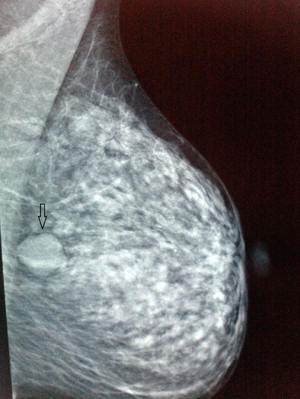

Hydatid Cysts In breast: Mammography And ultrasound Findings

Hydatid cysts in breast: mammography and ultrasound findings N TUTAR, MD, B CAKIR, MD, E GEYIK, MD, 48-year-old woman with palpable left breast lumps. Diagnostic mammogram, left mediolateral oblique (MLO) Germinal layer is trapped inside without cyst fluid representing ... Get Doc